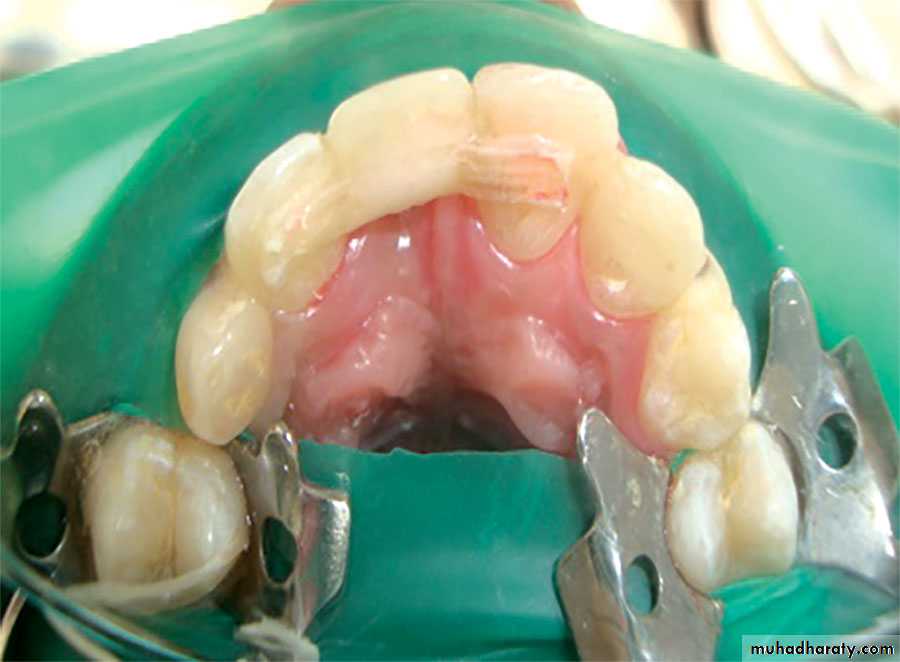

Fiber reinforced composite prosthesis

Prepared by : Mustafa moniem. Ari aso. Bahoz HimdadFiber-reinforced composite resin(FRC) prostheses offer the ad-vantages of good aesthetics, minimal invasive treatment, and an ability to bond to the abutment

teeth, thereby compensating for less-than-optimal abutment tooth retention and resistance form. These prostheses are composed of two types of composite materi-als: fiber composites to build the framework and hybrid or microfill particulate composites to create the external veneer surface

theses are organized into two categories: laboratory-fabricated prostheses chairside prosthesesLaboratory-fabricated FRC prostheses

can be retained by teeth or implants.include a surface that does not wear opposing tooth enamel ,and the FRC framework does not require waxing, casting, or soldeing procedures during fabrication.